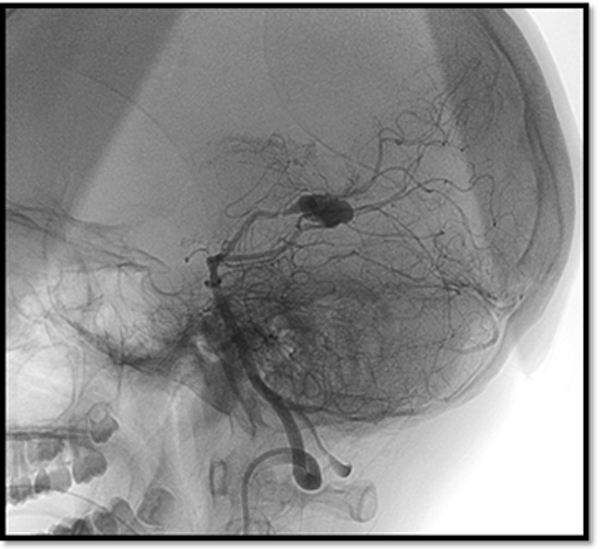

Se efectuó una craneotomía suboccipital lateral con evacuación del absceso cerebeloso. En la evolución, el paciente presentó un hematoma espontáneo secundario a la rotura de un aneurisma fusiforme del segmento P3 de la arteria cerebral posterior, confirmado por angiografía digital. El hallazgo fue interpretado como un aneurisma micótico, por lo que se realizó tratamiento endovascular. La resonancia magnética posterior a la embolización no evidenció aneurisma residual (Figuras 1 y 2).

Figura 1. Angiografía digital diagnóstica de vasos intracraneales. Se evidencia dilatación aneurismática del segmento P3 de arteria cerebral posterior derecha.

Figura 4. Angiografía digital cerebral, reconstrucción 3D: se observa dominancia de la ACA derecha con pasaje a través de la ACoA hacia la ACA izquierda. A nivel de la ACoA se identifica un aneurisma fusiforme que compromete toda su longitud y se extiende hasta el extremo proximal del segmento A2 izquierdo. Del domo aneurismático emerge una rama arterial.